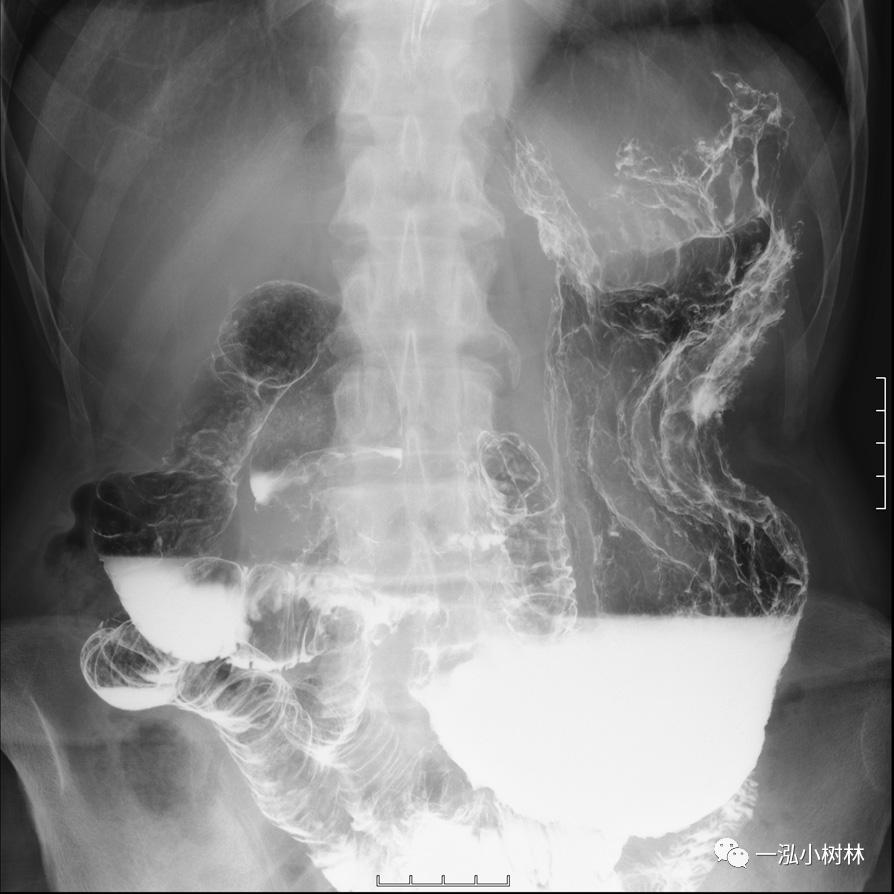

上消化道钡餐(图2):整个胃壁不规则伴随着变形,穹顶部变型明显,胃窦部也有变形。从食道、十二指肠到上部空肠有狭窄和通过没有发现障碍。

图2 上消化道钡餐:胃黏膜整体粗糙,胃壁壁不规则、变形。食管、十二指肠比肛侧的小肠没有发现狭窄和通过障碍。